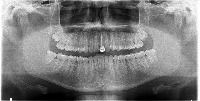

Dental Treatment Planning: The Dentistry computer vision model can be used by dentists and orthodontists for analyzing dental X-rays to identify teeth numbers and conditions like implant, root canal, or crown. By having automatic classification, it will improve the efficiency and accuracy of the treatment planning process.

Dental Education and Training: The model can be utilized as a learning tool for dental students, helping them to familiarize themselves with tooth numbering, implants, crowns, and root canals. This could be implemented in virtual classrooms or integrated into educational mobile applications.

Dental Insurance Claim Processing: The Dentistry computer vision model can be employed by insurance companies to automatically process dental claims. The model can identify the specific treatments or procedures (such as root canals or implants) from the dental X-ray images, leading to faster and more accurate claim processing.

Dental Record Management: Clinics and hospitals can use the Dentistry model to streamline their dental patients' record management by automatically categorizing X-ray images based on tooth number and treatment type. This will help in better organization of patient records and ease of access for future reference.

Dental Research and Analytics: The model can be valuable for dental researchers in the field of oral health analytics. By analyzing large datasets of dental X-ray images, the model can help identify patterns and trends for different treatments and tooth conditions, providing valuable insights for better oral care and health.